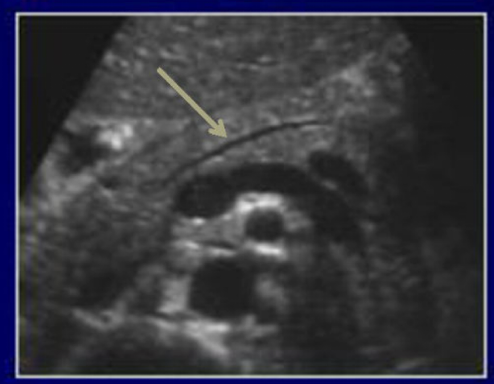

What is this image pointing to?

The pancreatic duct